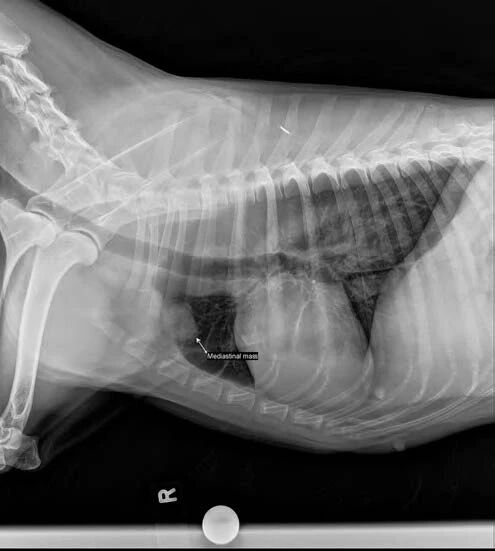

–纵隔肿块的存在应增加对与胸腺瘤相关的MG的怀疑(图3)。

图3. 侧位胸部X光显示纵隔肿块和巨食管。